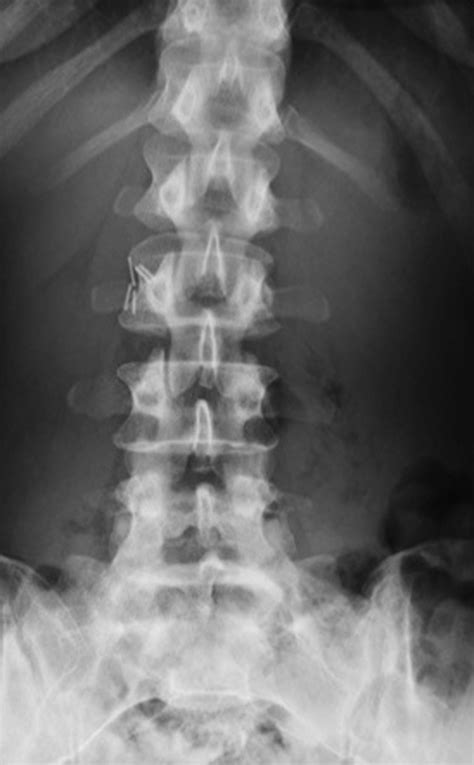

• X-rays: Provide a basic overview of the spine and can reveal the presence of transitional vertebrae.